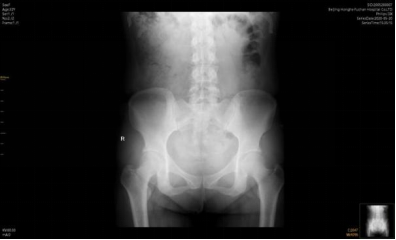

图片来源:网络

但总体一个原则,这些医生是有行医资格的,并且西医医生还会要求在治疗之前看骨盆的X光片。